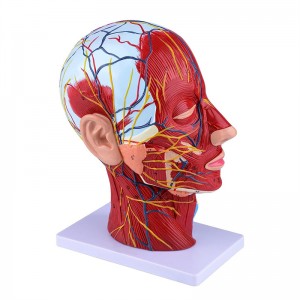

Modelo de anatomia de meia cabeça e pescoço humano modelo neurovascular superficial

Modelo de anatomia de meia cabeça e pescoço humano modelo neurovascular superficial

【1: 1 LifeSize】 Seção mediana de 1: 1 Modelo muscular vascular neural superficial grande de cabeça e pescoço natural (lado direito). Bem -estar. Oferecendo uma gama completa de recursos anatômicos.